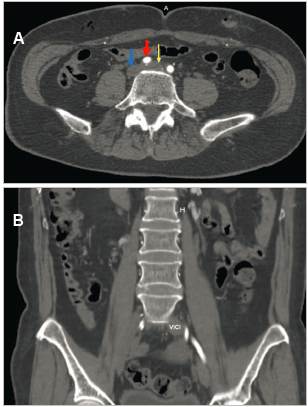

En la TAC de abdomen, se observó un incremento del calibre de la vena iliaca común izquierda que se extiende hacia la vena ileofemoral ipsilateral. Llamó la atención la aparente disminución de la luz de vena iliaca común por debajo de la AICD, evidenciando un trombo mural hacia confluencia de venas iliacas en vena cava inferior, concluyendo en trombosis de vena iliaca y vena ileofemoral izquierda, con sospecha de síndrome de May-Thurner (SMT) (Figuras 3a y 3b).

Figura 3 A (Arriba): compresión de vena iliaca común izquierda (flecha amarilla) por la arteria iliaca común derecha (flecha roja), condicionando dilatación de la vena (16 mm), con trombos murales en el interior. Vena cava inferior (flecha azul). B (Abajo): corte coronal abdomino-pélvico, evidencia trombosis de la vena iliaca común izquierda (VICI), con aumento de diámetro respecto a contralateral.